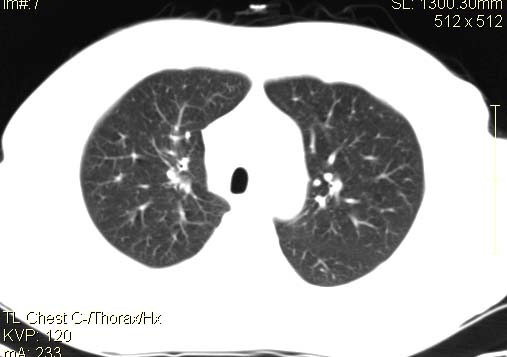

以下是引用qc80012345在2007-4-17 12:33:00的发言:[br]右肺下叶周围型肺癌伴肺门及纵隔内淋巴结转移;比较清楚。

以下是引用qingyuan在2007-4-17 14:19:00的发言:[br]右肺下叶外侧后段胸膜下区节结样病变、分叶、内可见空洞,壁厚薄不均,胸膜凹陷、肺门周围区纹理增粗、僵硬、并近似小结节样改变,肺门区软组织节结、纵膈淋巴结肿大,患者病史长、抗炎治疗无好转炎性改变基本排除,考虑:右肺下叶周围型肺癌伴纵膈及右肺门区淋巴结转移、肺内淋巴管受侵。